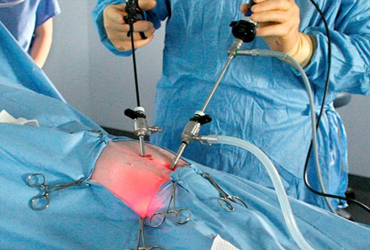

Advanced arthroscopic surgery through small incisions with specialised instruments lead to quick recovery with minimum scarring and less pain. Arthroscopic surgery is available for all joints.